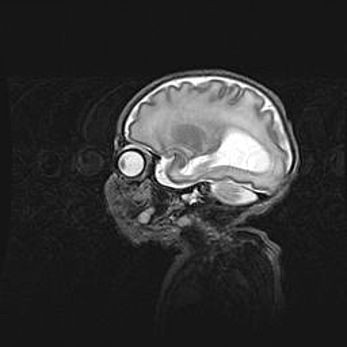

Мальформация Денди-Уокера. Киста задней черепной ямки.

Агенезия мозолистого тела.

Возраст: 2,5 месяца

Вес: 2420 г

Пол: женский

Окружность головы: 37 см

Срок гестации: 32 недели

Мальформация Денди—Уокера — редкий вид патологии ЦНС, представляющий собой врожденный порок развития каудального отдела ствола и червя мозжечка, ведущий к неполному раскрытию срединной (Мажанди) и латеральных (Лушка) апертур IV желудочка мозга. Для этогно синдрома характерна триада симптомов: гипотрофия червя мозжечка и/или полушарий мозжечка, кисты задней черепной ямки, гидроцефалия различной степени. В 70% случаев порок сочетается и с другими аномалиями головного мозга, в частности с агенезией мозолистого тела.